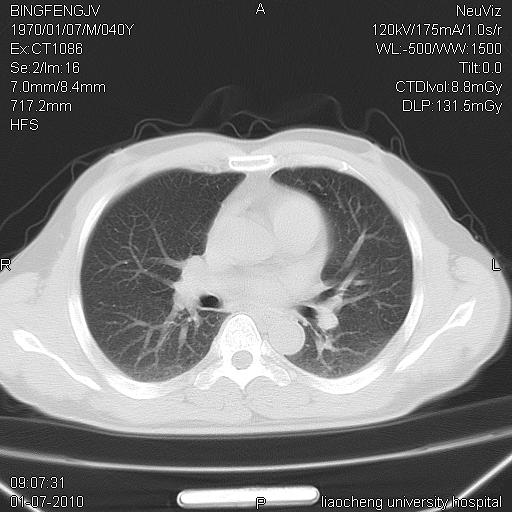

标题: CT23764B:男 40 肺部CT

治疗2周后

炎症性病灶,继发性改变。

考虑左肺上叶近胸膜下炎症并肺气囊形成。

炎症,大部吸收。